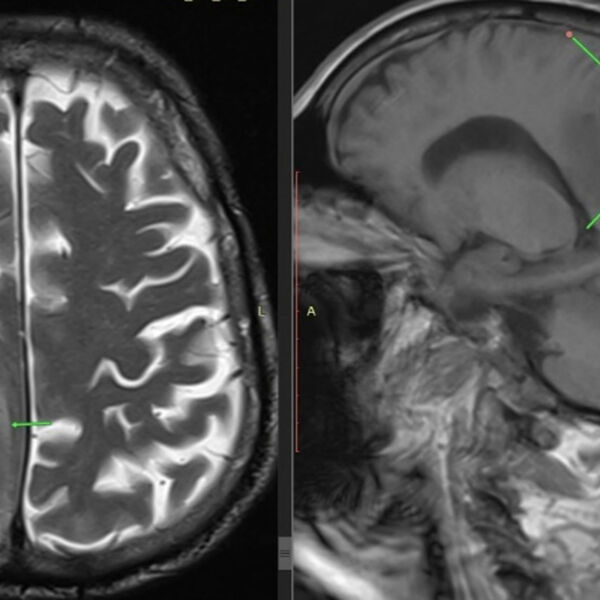

Российские врачи спасли пенсионера с опухолью мозга размером с лимон

В Пятигорске медики спасли 85-летнего мужчину, у которого в голове была опухоль размером с лимон. Об этом сообщает пресс-служба ГКБ Пятигорска.

Пожилого пациента доставили в больницу с симптомами, напоминавшими инсульт — у него отказала левая нога и парализовало левую половину тела. Врачи выявили причину недомогания мужчины. Оказалось, что у него в голове находится новообразование размером восемь на семь сантиметров.

Нейрохирурги провели пенсионеру костно-пластическую трепанацию черепа и полностью удалили опухоль. После вмешательства состояние мужчины быстро улучшилось, у него восстановилась двигательная активность. Гистология подтвердила доброкачественный характер удаленной опухоли.